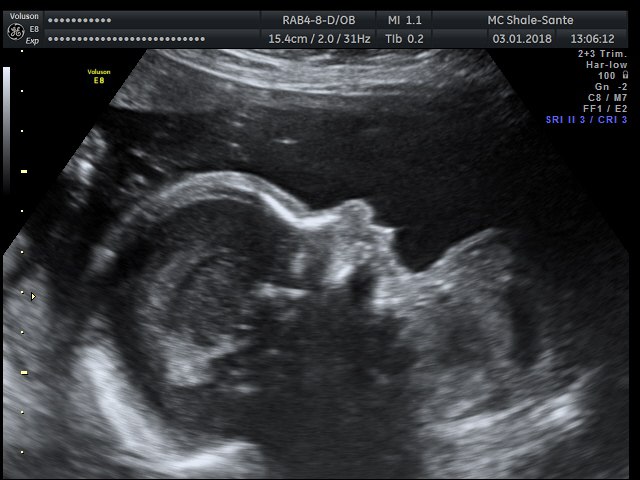

Нас померили,все все все посмотрели, все органы,врач про каждый рассказывала,притензий к нам нет, срок четко вообще совпадает пдр на 23 апреля)))

Весим уже 640гр,срок 24 недели и 3 дня. За 3 недели набрали 300 гр. Лежит косо,головой вверху,верится там как хочет))

Посмотрели мой шов,узистка сказала шов ювелирный,его даже почти не видно на матке,однородный,хороший,толщину сказала будет мерить уже после 36 недели))) поговорили с ней о родах,она говорит в краснодаре у нас почти не найти таких смельчаков,которые будут принимать ЕР после КС,тем лучше,я не очень хочу,хотела бы ПКС.